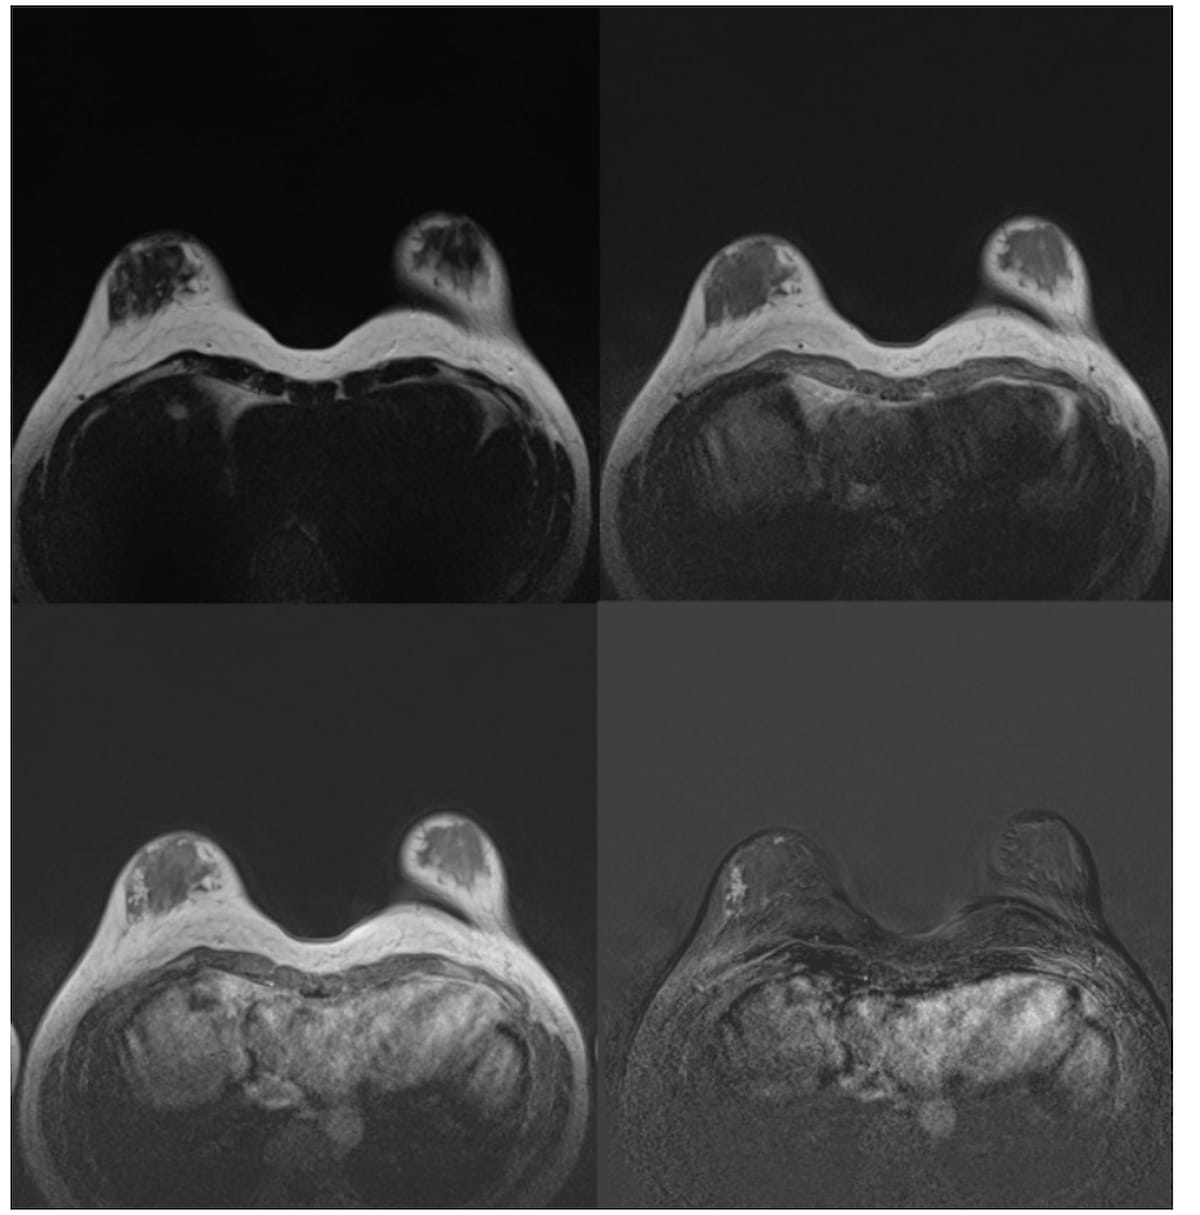

For the prediction of axillary lymph node metastasis in patients with breast cancer, an MRI-based, 4D convolutional neural network model demonstrated an AUC of 87 percent and sensitivity of 89 percent, according to new research.

An MRI-based machine learning model demonstrated a comparable background parenchymal enhancement (BPE) hazard ratio to that of manual BPE assessment for breast cancer, according to a study of over 4,500 women with dense breasts.

In a new literature review, researchers noted key findings on the use of breast MRI in facilitating breast cancer detection for women with dense breasts and others at high-risk for breast cancer.

In a study of nearly 2,500 women with BRCA1 or BRCA2 sequence variations, researchers found that MRI surveillance led to a 3.2 percent breast cancer mortality risk at 20 years in contrast to a 14.9 percent mortality risk for those who did not have MRI surveillance.